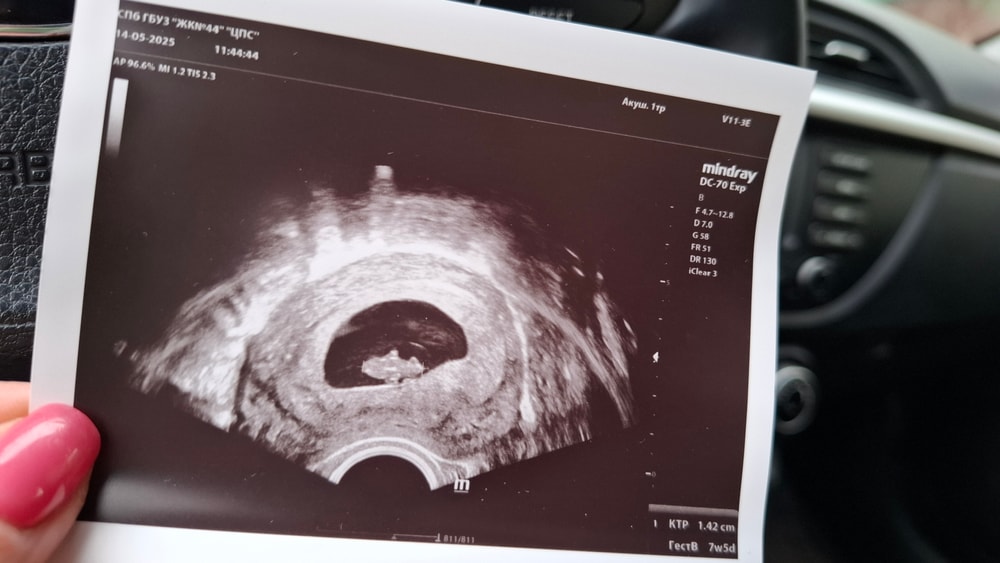

Сегодня 35 дпп, крио, второе узи. Есть размер человека, сердцебиение. Развитие, прогресс таки, полноценная беременность, ого-го и не хухры-мухры, хорошие 7 недель и 5 дней. Всё красивое, ре понравилось. Силуэт маленькой акулы :) или мармеладного мишки :)

14.05.2025